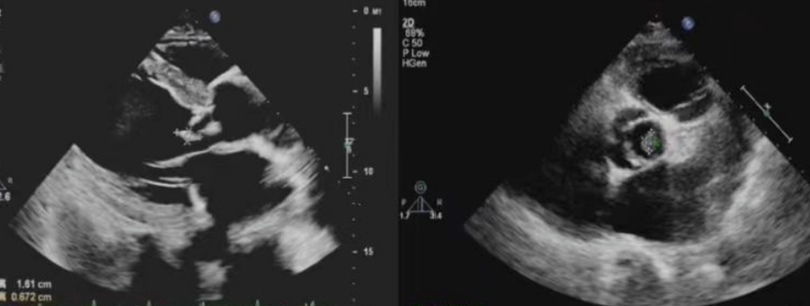

32 岁的王先生,因为拔牙后没注意护理,开始反复发烧,吃了退烧药也不管用,还总觉得心慌、没力气。医生怀疑是细菌通过拔牙伤口钻进了血液,流到心脏引发了感染,在经胸超声(TTE)检查时发现,他的主动脉瓣上,长了一个绿豆大小的「小疙瘩」——这是细菌形成的赘生物。同时还看到,因为这个小疙瘩的破坏,主动脉瓣关不严实,血液出现了反流。结合验血结果(查到了相同细菌),医生很快确诊了王先生病症属于「感染性心内膜炎」。

55 岁的李阿姨,患有多年风湿性心脏病,因最近突然出现高烧、呼吸困难,手指尖还长了紫红色的小疹子,她来到了医院, 医生通过经食道超声(TEE)检查后发现,她的二尖瓣后叶上,藏着一个米粒大小的「小疙瘩」,而且瓣膜已经被蛀出了一个小洞,还连累周围心肌长了个「小脓包」(瓣周脓肿)。原来,李阿姨也是得了感染性心内膜炎。

就像王先生的「米粒大赘生物」、李阿姨的「芝麻大隐藏病灶」,只有超声能直接看到这些感染的「证据」,结合验血结果,才能快速确诊,避免漏诊、误诊。

超声不仅能找「小疙瘩」,还能看它把瓣膜破坏到啥程度——是轻微反流,还是像李阿姨那样出现「破洞」「小脓包」,这些信息直接决定医生是选药物治疗,还是要做手术。

- 经胸超声(TTE):像王先生这样的初诊患者,先做这个「无创检查」——探头贴胸口,不痛不麻烦,能快速排查明显病灶,是首选的「初筛工具」。

- 经食道超声(TEE):李阿姨这样,经胸超声没发现问题但症状典型,或需要精准看瓣膜损伤、找隐藏病灶时,就用这个「高清工具」,能揪出 95% 以上的微小病灶。